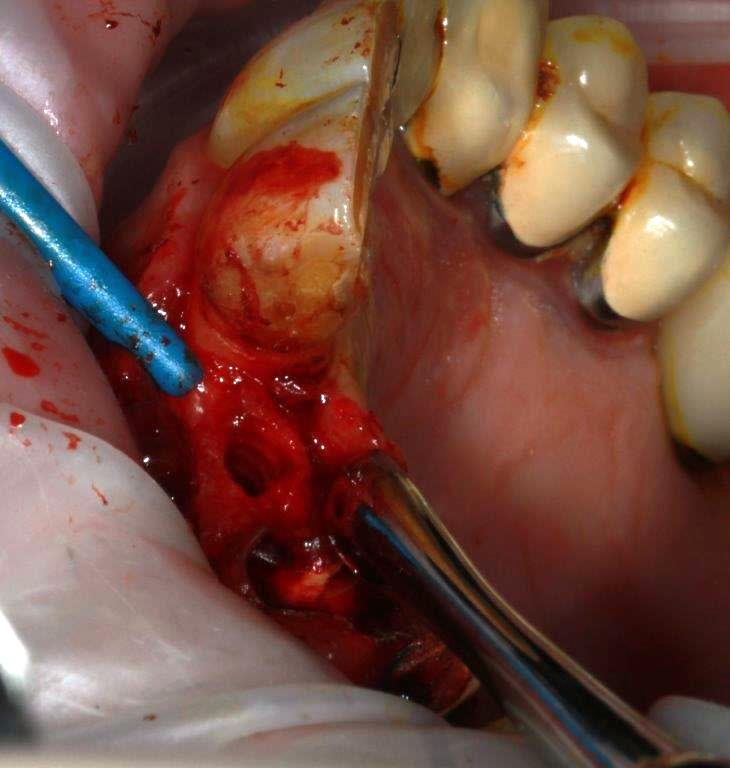

-Alors comme je suis de cet avis je me lance, avec un cas tout bête d'expansion, patient 70 ans, non fumeur, porteur d'un bridge 12/13/14, 13 et 14 en fin de vie, difficile de laisser le patient sans dents, et pas envie d'une EIIM, je décide de tenter la dépose/ repose du bridge, et de poser un implant en 12 os fin bonne qualité, je n'ai pas le scan ici je vous le passerai ultérieurement.

la difficulté est de corriger l'axe

spreaders A/B/C/D/E après avoir scindé la crête à la lame N° 11 (sur 12 à 15mm)